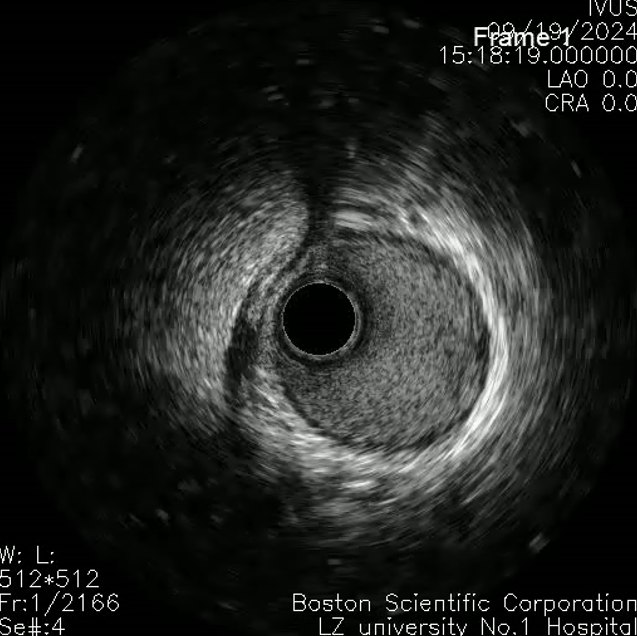

左主干-回旋支行IVUS检查;

回旋支近中段可见弥漫性狭窄伴有360°环形钙化;

回旋支开口面积2.1平方毫米;

左主干-前降支IVUS导管不能通过。